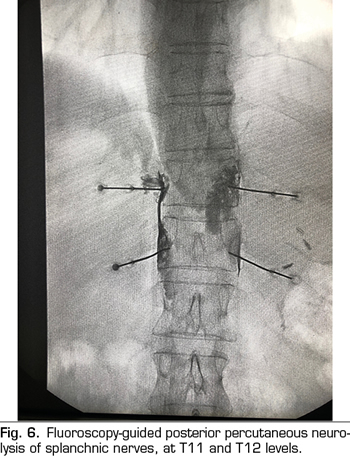

The splanchnic nerves are three nerves that are born from the thoracic sympathetic chain and are arranged laterally in the spine: 1) The greater splanchnic nerve is formed by the sympathetic preganglionic fibers from T5 to T9, 2) the minor splanchnic is formed by the fibers from T10 and T11, and 3) the inferior splanchnic, by the fibers coming from T11 and T12. All of them converge on the lateral face of the T11 and T12 vertebrae - ideal place for the performance of a neurolysis - and run parallel until they cross the diaphragm and join the celiac plexus.

The percutaneous technique is performed using a retrocrural posterior approach, usually guided by fluoroscopy (Figure 6). The lesions can be performed by conventional radiofrequency or using neurolytic agents as in the celiac plexus.